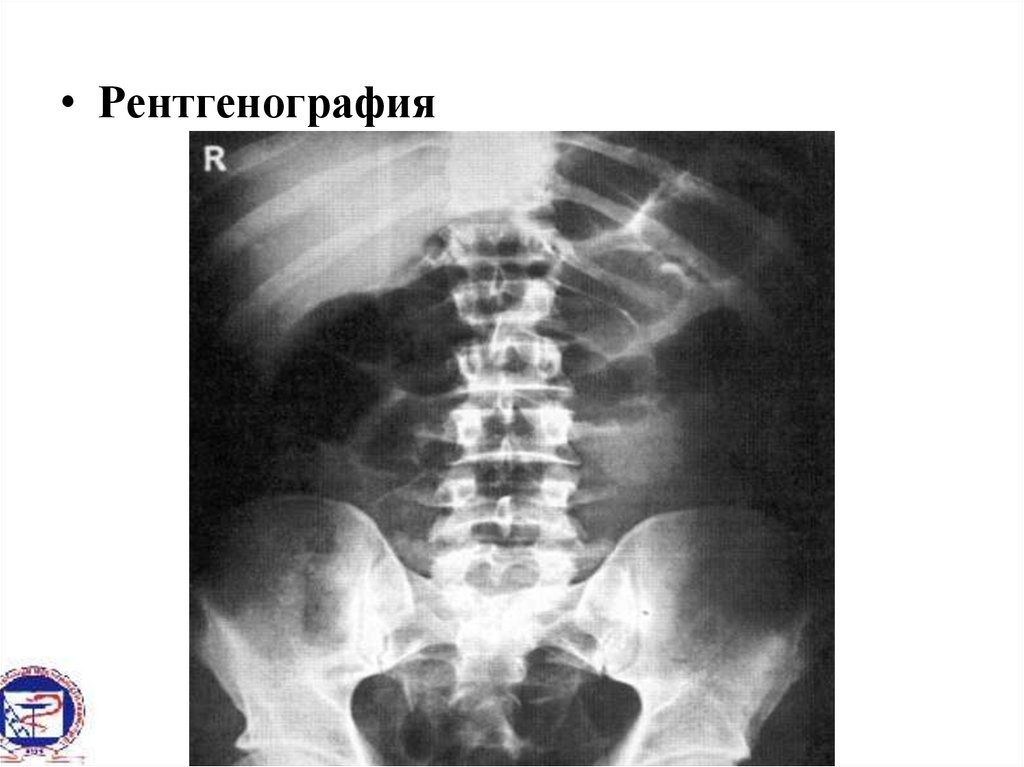

• Рентгенография